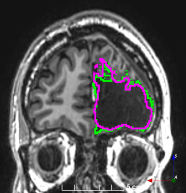

(f)

Figure 3: Manual labels from Rater A (green) and Rater D, the model trained with PubFull + EpiPre + Pseudo (magenta). Errors caused by a (a) small resection, (b) blood clot in cavity and (c) brain shift; segmentations corresponding to the (d) 50th, (e) 75th and (f) 100th percentiles giving a DSC of 81.7, 86.5 and 93.8, respectively.

We trained a model using PubFull, EpiPre and Pseudo (2371 images), obtaining a DSC of 81.7 (14.2). Adding the pseudo-labels to PubFull and EpiPre did not significantly improve performance (p=0.176𝑝0.176p=0.176), indicating our semi-supervised learning approach provided no advantage. Predictions from this model are shown in Fig. 3.

Predictions errors are mostly due to 1) resection of size comparable to sulci (Fig. 6a), 2) unanticipated intensities, such as those caused by the presence of blood clots in the cavity (Fig. 6b), 3) brain shift (Fig. 6c) and 4) white matter hypointensities (Fig. 6e). Further work will involve using different internal and external cavity textures, carefully sampling the resection volume, simulating brain shift using biomechanical models, and quantifying epistemic and aleatoric segmentation uncertainty to better assess model performance [24].